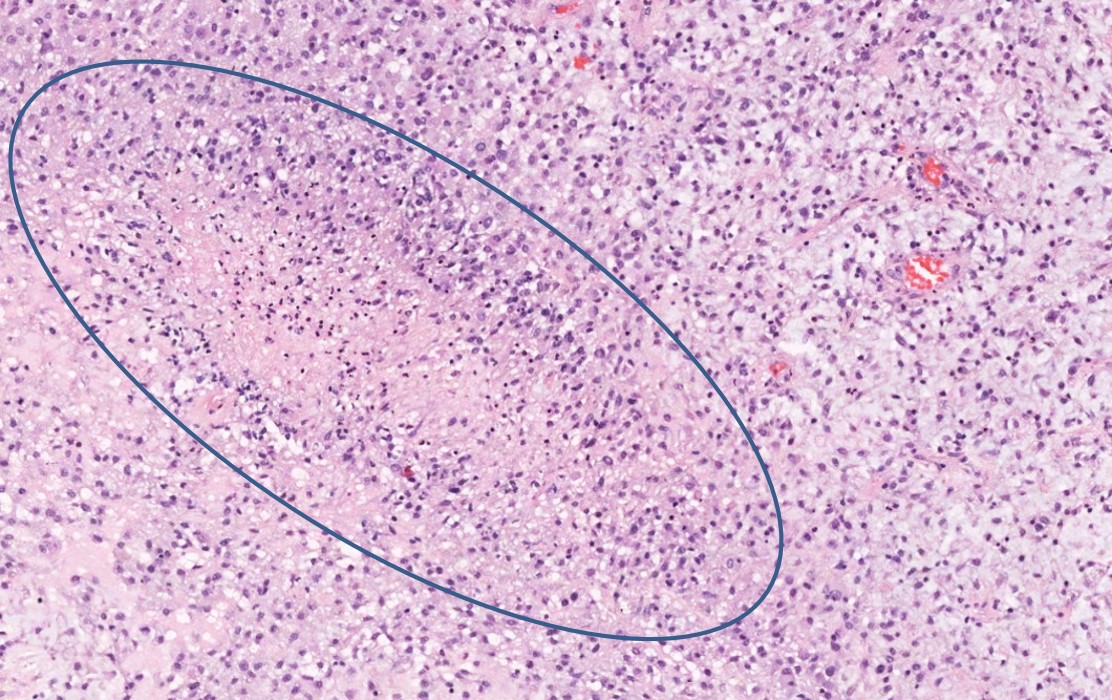

Микрофотографии гистологии глиобластомы головного мозга